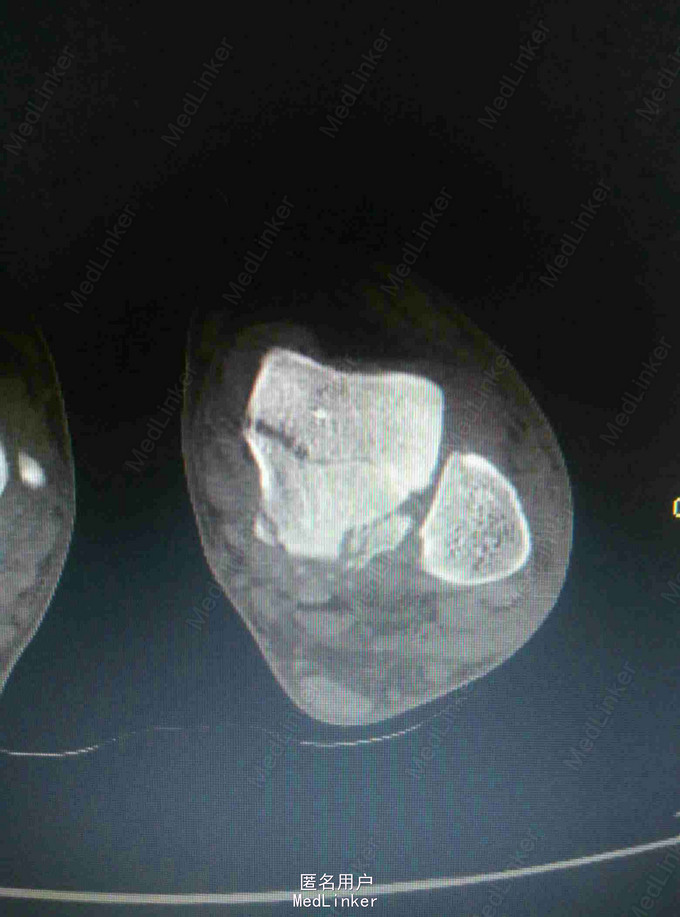

距骨骨折采用外踝截骨入路显露固定手术

完善X线片及CT扫描检查

行外踝截骨入路显露复位螺钉固定术